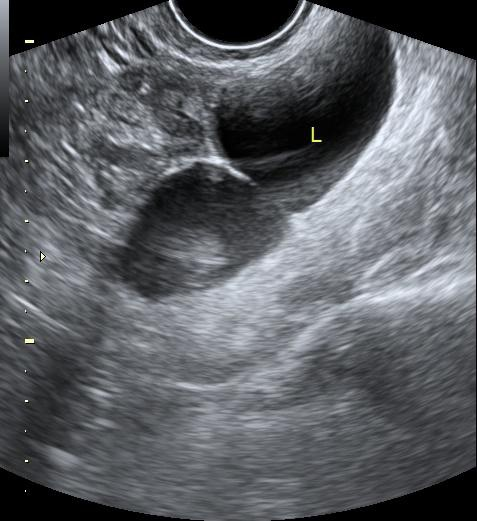

US imaging presents a substantial domain gap compared to other medical imaging modalities; building an US-specific foundation model therefore requires a specialized large-scale dataset. To build such a dataset, we crawl a multitude of platforms for human medical US with instance annotations and open-access availability: Papers with Code, Google Dataset Search, GitHub, Google Scholar, Kaggle, ResearchGate, Mendeley dataset, Zenodo and Data in Brief. Through this process, we arrive at US-43d (see Fig.1.a), a collection of 43 datasets covering 20 different clinical applications, containing 282,321 annotated segmentation masks from both 2D and 3D scans. US-43d captures organs and lesion of various shapes, sizes, and textures across clinical applications such as cardiac, fetal head, thyroid, and breast lesions, as illustrated in Fig.2, providing a comprehensive view of the medical ultrasound landscape. Table 1 provides detailed information on the US-43d dataset, including dataset names, access links, and the number of images and segmentation masks available in each.

For testing, we select three diverse datasets from US-43d: BUS-BRA [BUSBRA] (breast lesions, 1875 images), MMOTU2D [mmotu] (ovarian lesions, 1469 images), and GIST514-DB [GIST514] (gastrointestinal stromal tumors, 514 images). GIST514-DB is included as an outlier in our selection, as it is the only dataset in US-43d with radial acquisition. We evaluate on the official test split of each dataset. Together they include linear and radial probes, endoscopic and non-endoscopic US, and span multiple clinical applications, anatomical regions, lesion types, and imaging techniques, enabling exhaustive evaluation of UltraSam’s generalizability. We reserve 5% of each training dataset for validation and use the remaining 95% for training. We preprocess images by removing label-background overlaps (common in 3D US), cropping backgrounds occupying more than 50% of image pixels, and using sagittal views for 3D images.